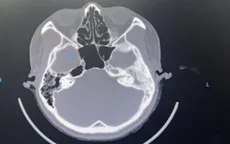

VTV.vn - Nữ bệnh nhân 29 tuổi vào viện khám vì đau và chảy mủ tai trái thường xuyên, tự mua thuốc uống không đỡ.